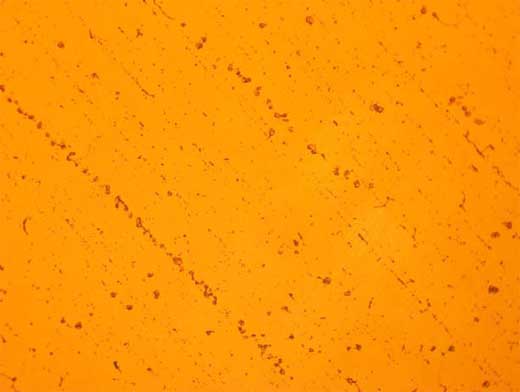

Análisis Histológico: Plasma Pobre en Plaquetas solo. Visualizamos material microfibrilar, elementos celulares aislados y hematies rotos.

Análisis Histológico: Plasma Pobre en Plaquetas con Cloruro de Calcio al 10%. Visualizamos Plaquetas aisladas, cristales de calcio y material microfibrilar.